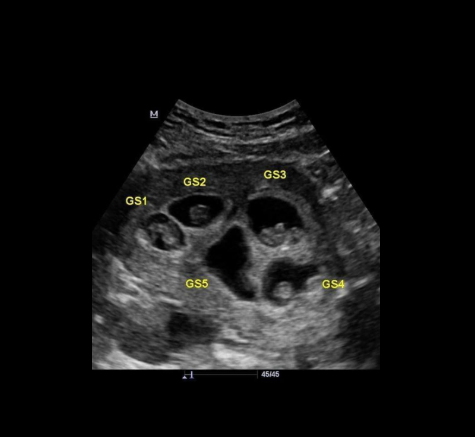

ЭЕРЭГ: Монголын анхны таван ихэр хүүхэд удахгүй мэндэлнэ